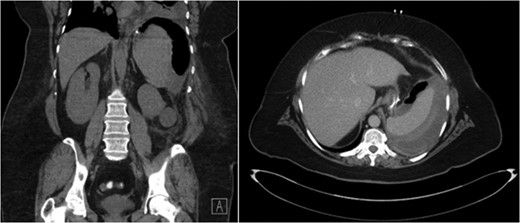

She represented 8 days after discharge with complaints of left upper quadrant abdominal pain. She denied dizziness, shortness of breath, chest pain or trauma to her abdomen. On physical exam her heart rate (HR) was unchanged from discharge at 104 bpm; however, she was noted to be hypotensive with a blood pressure (BP) of 86/44 mmHg and oxygen saturation 98% on 3 l. She received multiple fluid boluses in the emergency department and while her HR remained elevated at 104 bpm, her BP increased to 124/79 mmHg. A computed tomography (CT) scan with oral and intravenous contrast was obtained and demonstrated a large mixed attenuation fluid collection with scattered pockets of air within the splenic capsule without evidence of free intra-peritoneal air (Fig. 1). Upon laboratory analysis she was without a leukocytosis and her hemoglobin was decreased; however, unchanged from her previous discharge. It slowly declined throughout her readmission. On post-operative Day 12 her hemoglobin (Hgb) was 7.8, and she received two units of packed red blood cells with an appropriate increase in her Hgb. After initial transfusion of two units of packed red blood cells her hemoglobin and vital signs remained stable.

CT abdomen demonstrating air and fluid contained with the splenic capsule.